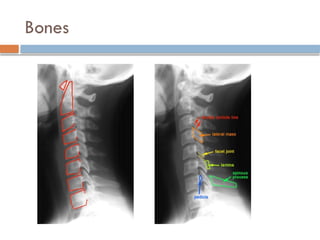

Interpretation of Lateral Plain Film

 Mnemonic AABCS

 Adequacy

 Alignment

 Bones

 Cartilage

 Soft Tissue

Interpreting lateral Plain Film

 Alignment

 Anterior vertebral line

 Formed by anterior borders of vertebral bodies

 Posterior vertebral line

 Formed by posterior borders of vertebral bodies

 Spino-laminar Line

 Formed by the junction of the spinous processes and the laminae

 Posterior Spinous Line

 Formed by posterior aspect of the spinous processes

Bones